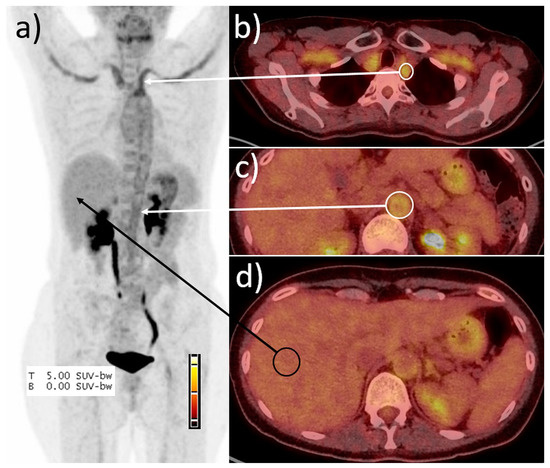

Figure 1.

Example of the peak SUV ratio determination. (a) Maximum intensity projection, (b–d) fused PET/CT images. Calculation of the SUVratio exemplified in patient #15. SUVmax in the left subclavian artery (white circle, b) was 3.7, in the abdominal aorta (c) 2.1, and in the right liver lobe (black circle) SUVmean was 1.6, resulting in a SUVratio of 2.2 in maximum. In consequence, the scan was scored positive for vasculitis.